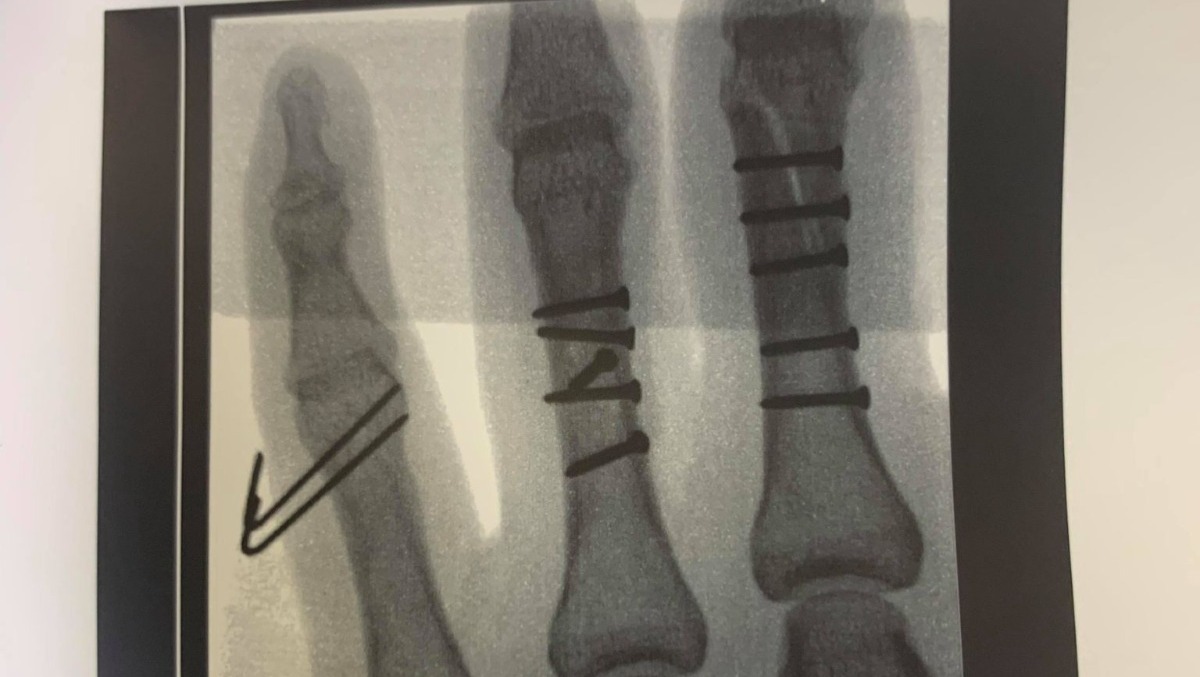

Tuesday's surgery was a success. Once the surgeon began, he quickly realized the damage was more extensive than the x-rays showed. What was supposed to be a 2-hour surgery ended up taking over 6 hours. They had to reconstruct my middle and ring finger, with 11 screws and 2 pins in my pinky finger.